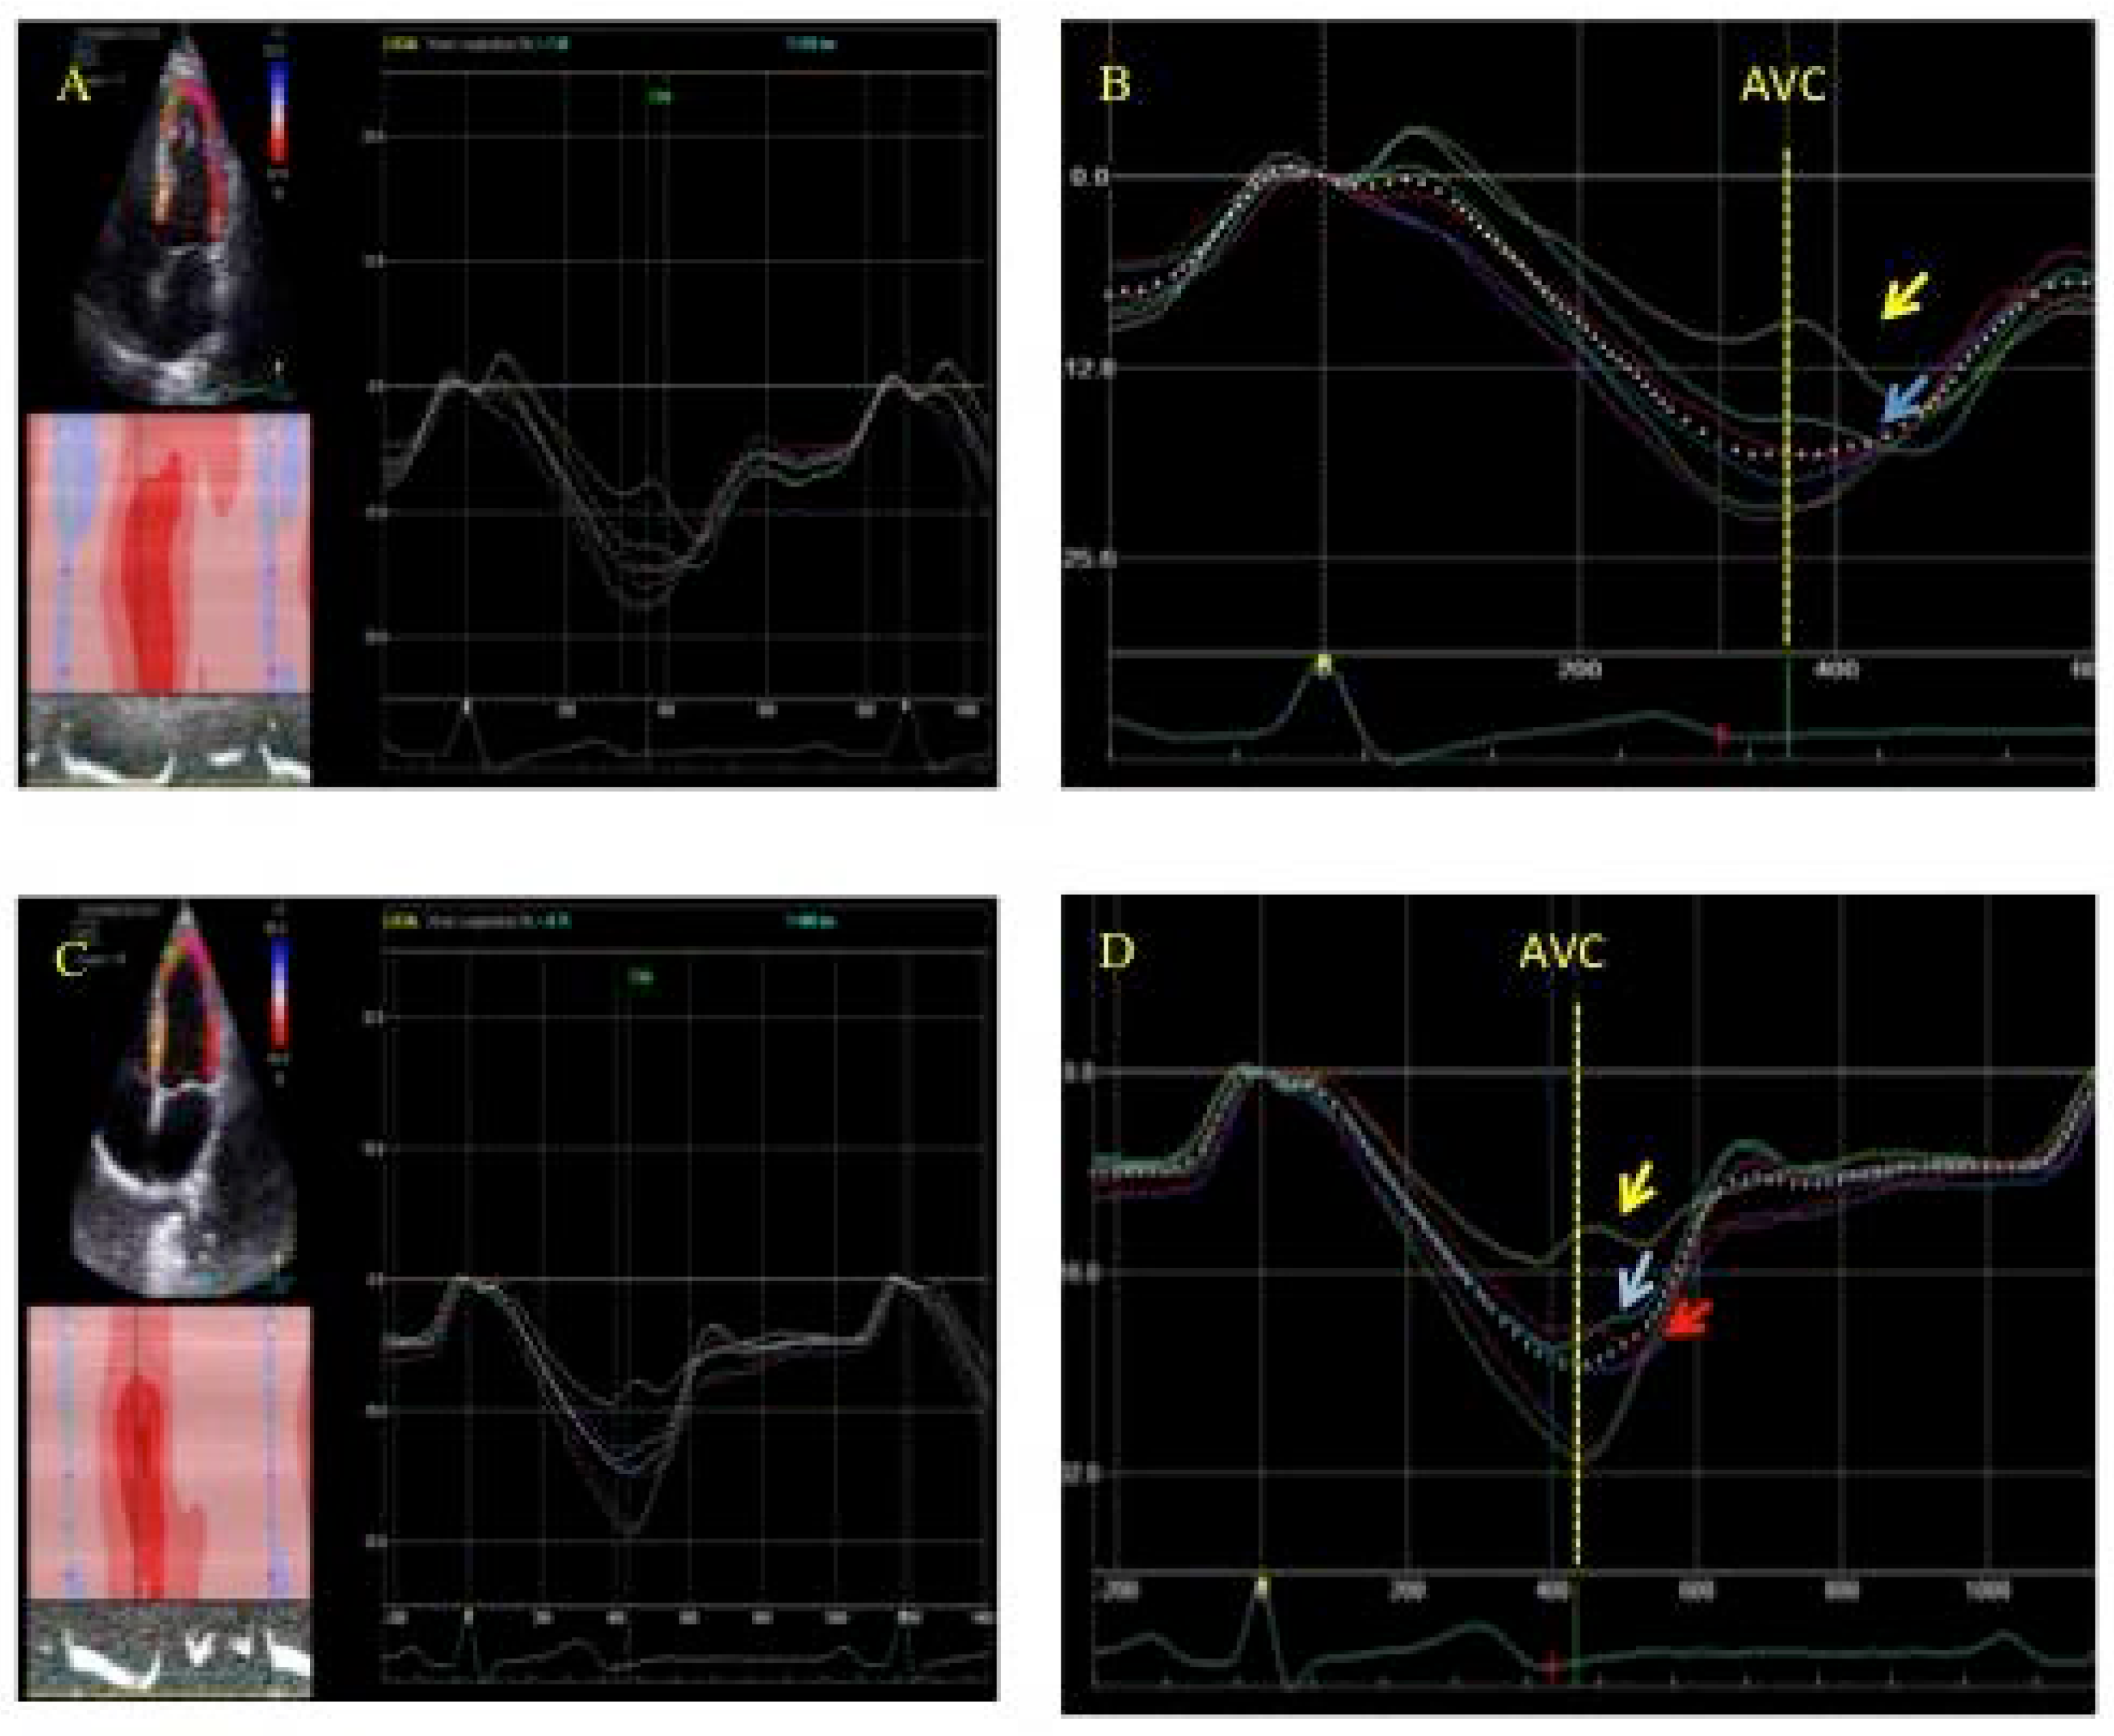

3.1. Postsystolic Shortening